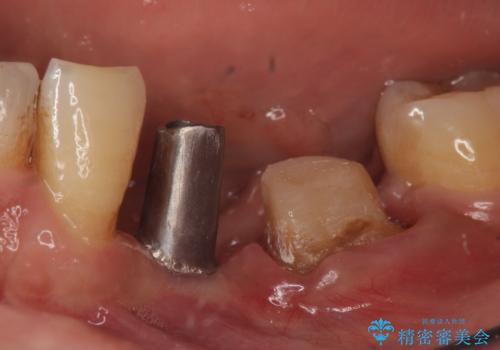

インプラント 左下奥歯の咬み合わせの改善

- 左下の歯並びが悪く、左側で物が咬みにくいので診て欲しいといらっしゃった方の症例です。

歯列矯正は御希望されなかったため左下4、5番目の歯を抜歯し、インプラントによる欠損補綴を行いました。

ストローマンについて

当院では主にストローマンという種類のインプラントを治療に用いています。

ストローマンは世界的にもNo1のシェアを誇り、骨との適合にも優れたインプラントです。

カスタムアバットメントについて

カスタムアバットメントは患者様それぞれの歯茎に合わせて製作されたオーダーメイドのアバットメントです。

既製のアバットメントに比べ適合がよく、高い清掃性を誇ります。